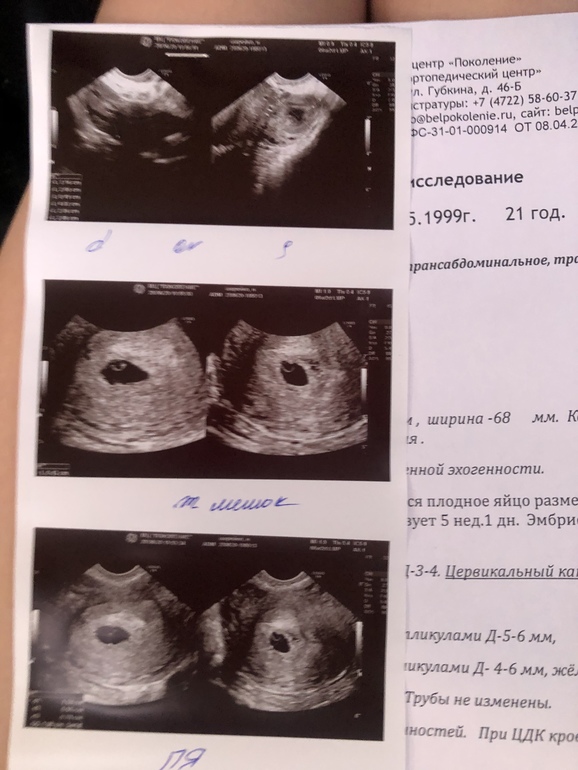

У вас пя СВД 16+9+8 /3 = 11 мм и соответствует 6 ти неделям,но по размеру пя они срок вообще не ставят,пишут обычно беременность малого срока,если эмбрион есть,то ставят уже срок по размеру эмбриона,рано ещё вы пошли,через неделю все найдут,и пя подрастет и эмбрион появиться

Плодное яйцо на 5 недель 1 день - эмбрион может быть размером 1 мм, его не видно еще. Не переживайте,ведь есть желточный мешок,это хороший знак!

По хгч у меня вообще ошибка была) они не верные результаты мне отдали) по месячным , были последние 15.05.20, а узист говорит, что плодное яйцо меньше на неделю , потому что нет эмбриона

Я просто переживаю, говорят уже на 6-7 можно сердечко послушать, а мне говорят что даже эмбриона не видят) переживаю все ли ок, потому как неделю назад мое узи и там в разы меньше и плодное яйцо было и вообще точка маленькая была!